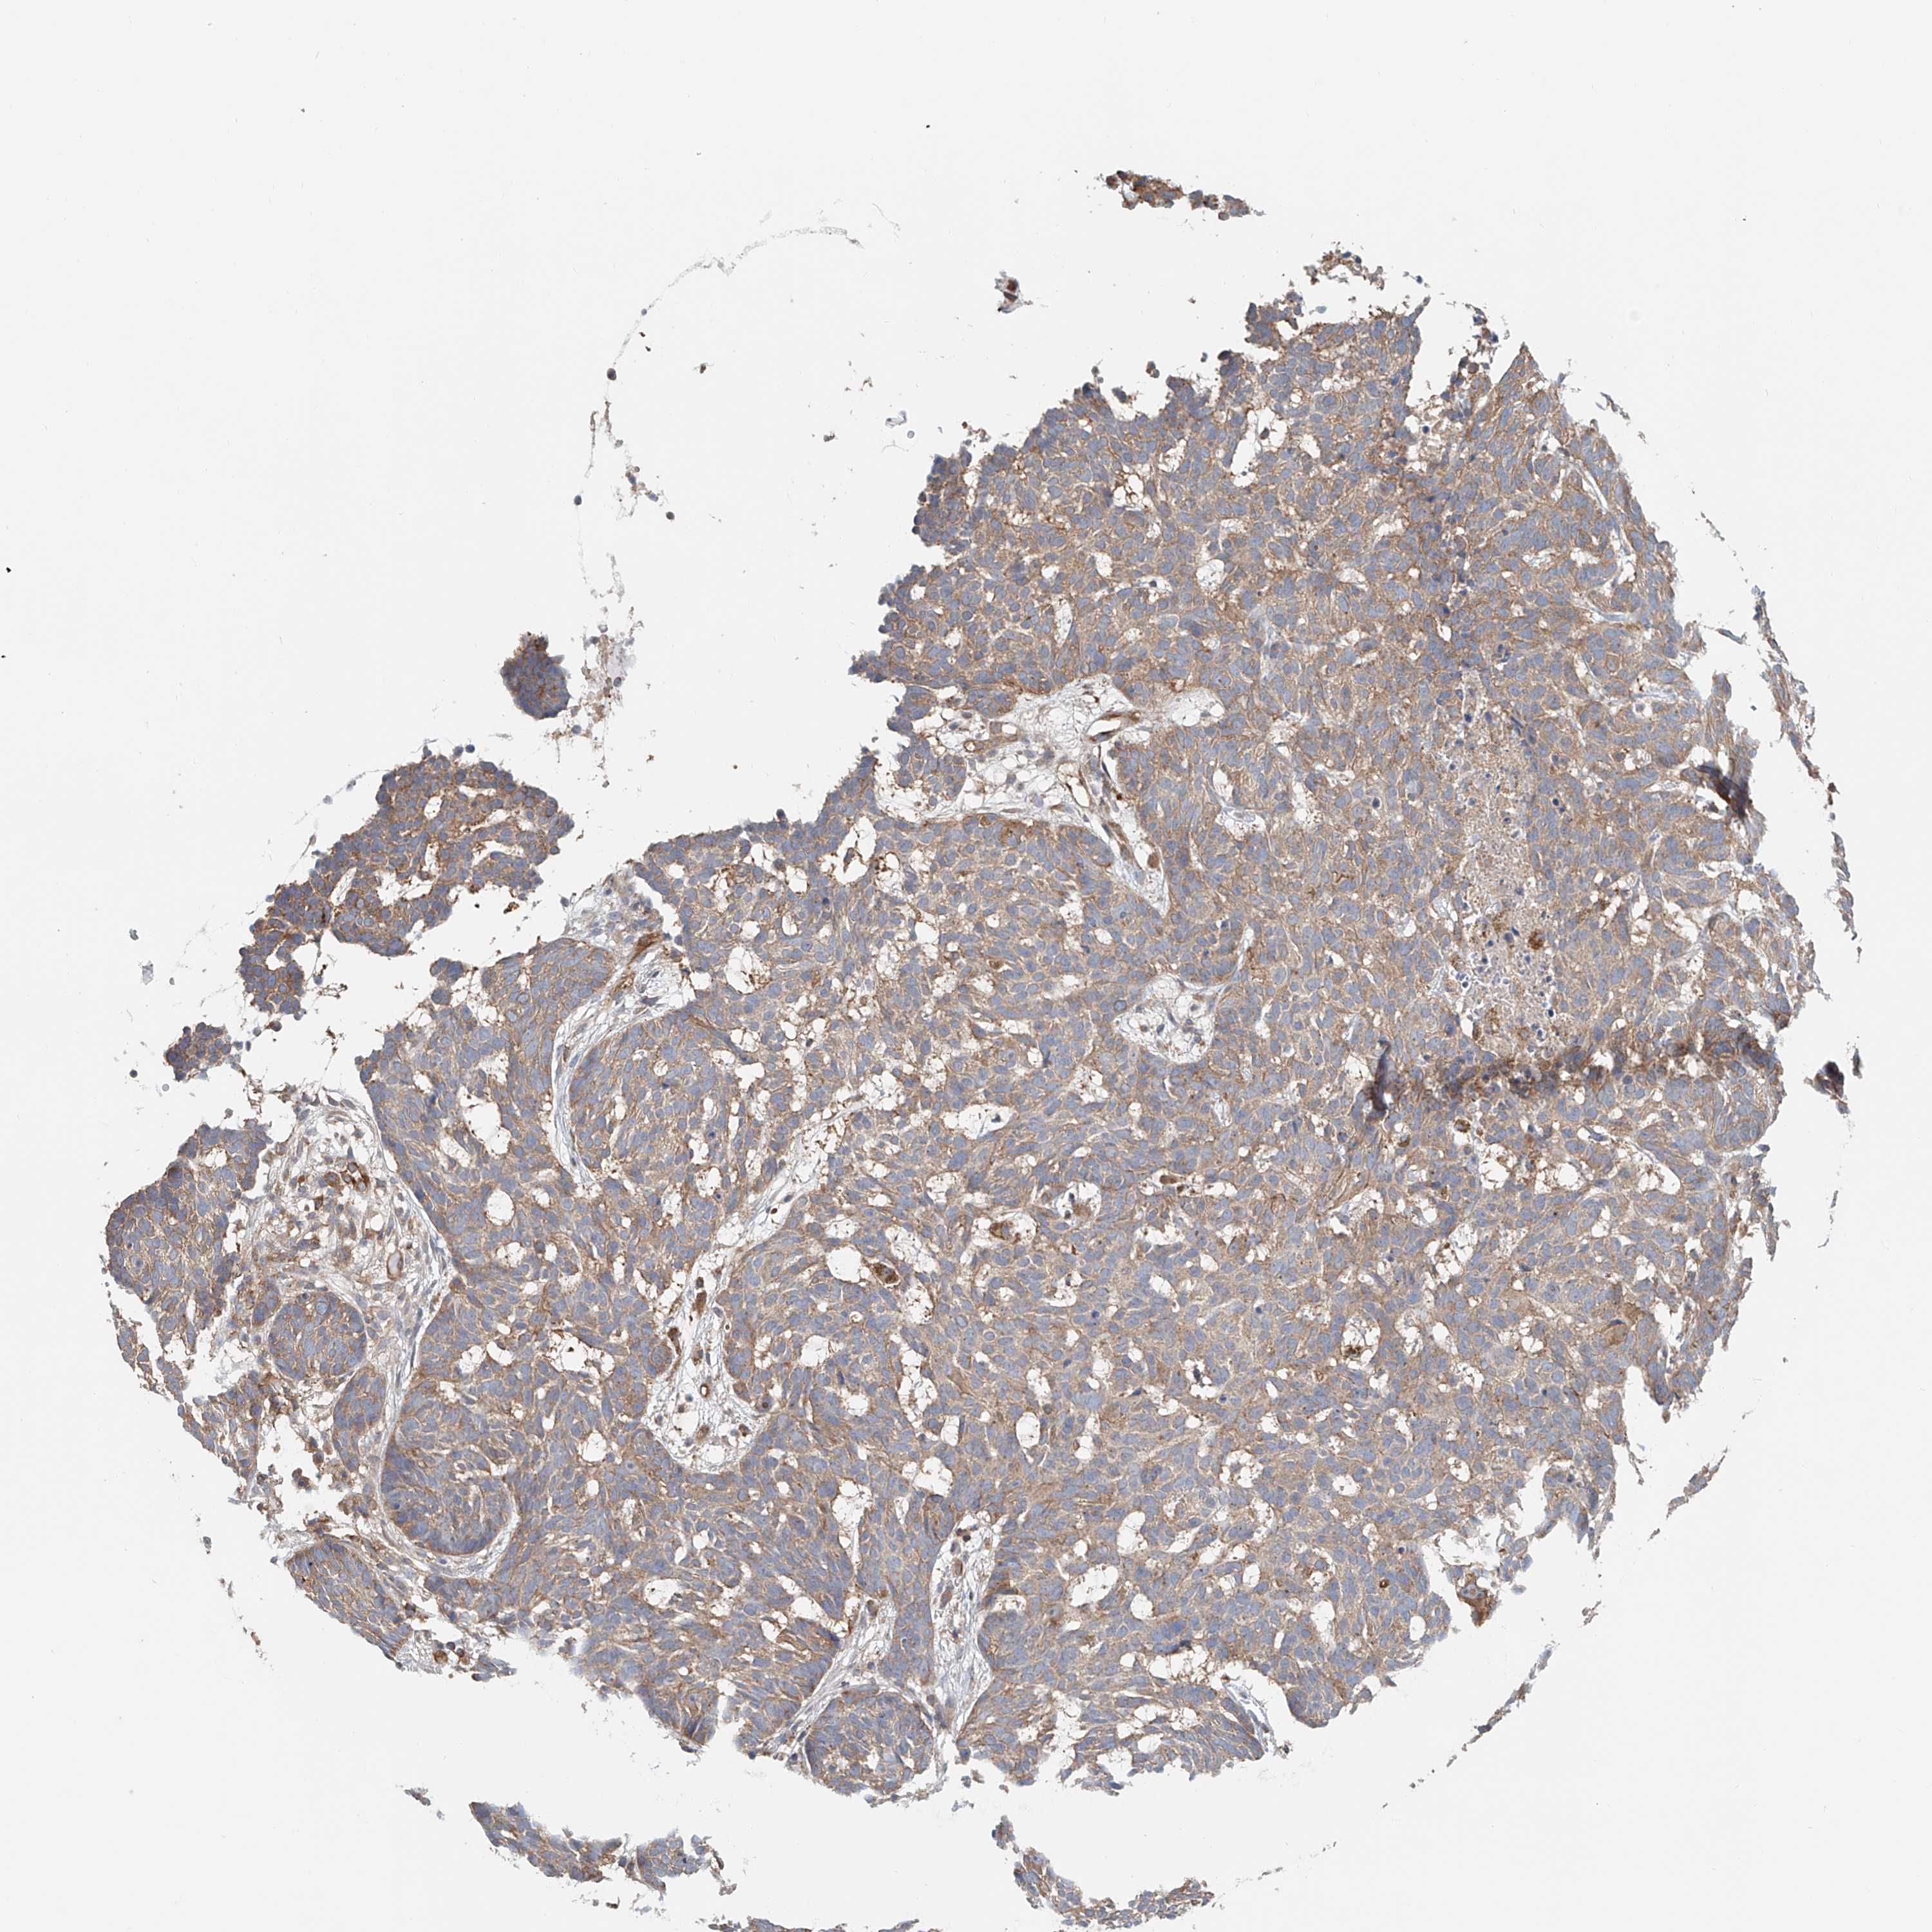

Basal cell and squamous cell cancer

SKIN CANCER - Protein expressioni

A mouse-over function shows sample information and annotation data. Click on an image to view it in a full screen mode. Samples can be filtered based on level of antibody staining by selecting one or several of the following categories: high, medium, low and not detected. The assay and annotation is described here.

Antibody stainingi

Antibody staining in the annotated cell types in the current human tissue is reported as not detected, low, medium, or high, based on conventional immunohistochemistry profiling in selected tissues. This score is based on the combination of the staining intensity and fraction of stained cells.

Each image is clickable and will lead to virtual microscopy that enables deeper exploration of all samples and also displays staining intensity scores, fraction scores and subcellular localization as well as patient and tissue information for each sample.

Antibody HPA031106

Antibody HPA031107

Staining

High

Medium

Low

Not detected

Intensity

Strong

Moderate

Weak

Negative

Quantity

>75%

75%-25%

<25%

None

Location

Nuclear

Cytoplasmic/membranous

Cytoplasmic/membranous,nuclear

Squamous cell carcinoma, NOS